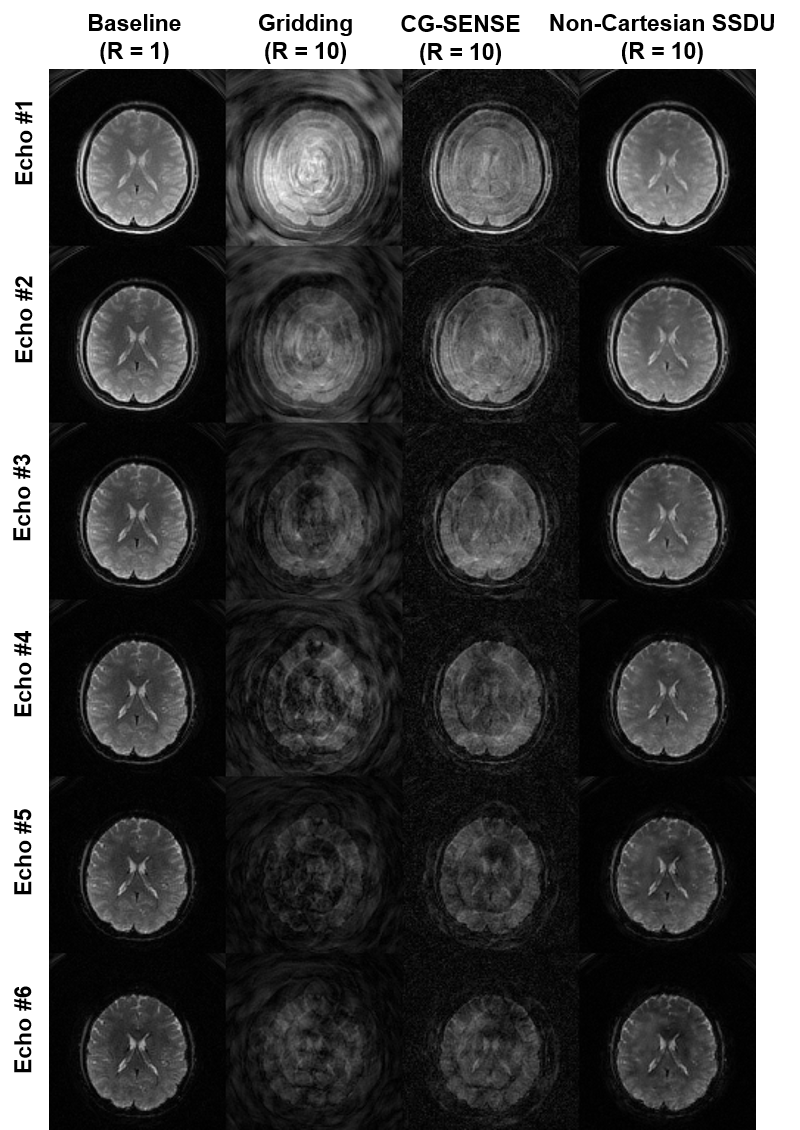

Refer to caption

Fig. 2: Reconstructions from a representative slice of R=10absent10=10= 10 multi-echo spiral data. Gridding and CG-SENSE fail at this high-acceleration rate, while non-Cartesian SSDU gives good reconstruction close to the baseline with 10 spiral arms (R=1absent1=1= 1). Note that this dataset is from training acquisitions (described in Section 2.3), and not from an fMRI time series, as R=1absent1=1= 1 acquisition would be impossible in the latter setup with this spatiotemporal resolution.

Figure 2 shows representative reconstruction results of a 10-fold accelerated multi-echo spiral sequence. As aforementioned, these data come from the first set of acquisitions, which do not contain a time series or an fMRI experiment. As such, it is possible to acquire a baseline image (R=1absent1=1= 1) with a segmented acquisition containing 10 spiral arms. At the target R=10absent10=10= 10 acceleration, gridding and CG-SENSE yield poor reconstruction quality as expected. PD-DL trained with non-Cartesian SSDU provides substantial improvements, closely matching the R=1absent1=1= 1 baseline.